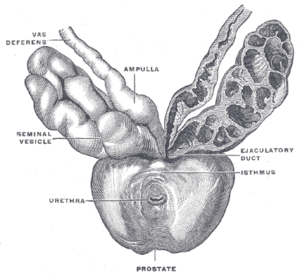

Prostate with seminal vesicles and seminal ducts, viewed from in front and above. | |

Fundus of the bladder with the vesiculæ seminales. Vesiculae seminales and ampullae of ductus deferentes, front view.

Vesiculae seminales and ampullae of ductus deferentes, front view. Vertical section of bladder, penis, and urethra.